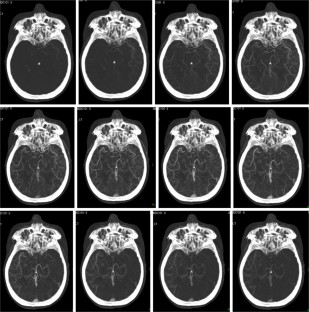

A practical protocol for shortening reconstruction time of volumetric data and imaging bilateral middle cerebral arteries for thrombectomy in acute ischemic stroke using an 80-row computed tomography scanner

Time-consuming reconstruction of volumetric data by area-detector-computed tomography (ADCT) scanning and narrow coverage of small-row ADCT may hinder volumetric scanning in acute stroke stage. To design a practical protocol of volumetric scanning for thrombectomy using an 80-row ADCT. An imaging protocol that focuses on the middle cerebral arteries by tilting the gantry of an 80-row ADCT with 0.5-mm-thick detectors can shorten the reconstruction time by 1.0-mm thickness scanning without subtraction. The reconstruction time of small volumetric data was 69 second. This practical protocol is applicable before thrombectomy in different stroke centres with narrow-coverage ADCT scanners.

Fig. 1

Fig. 2